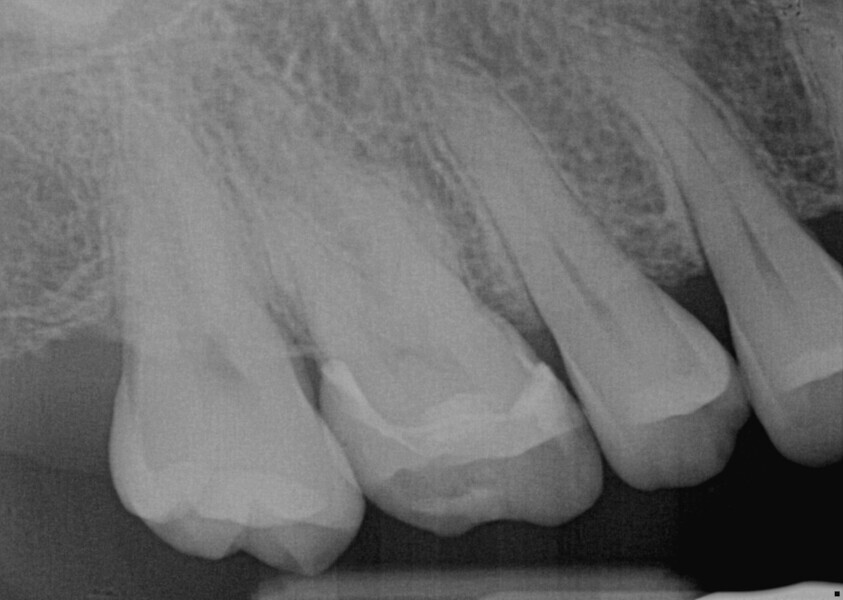

A 23-year-old female patient presented with cold sensitivity of the teeth in the maxillary right posterior sextant. Examination noted old composite fillings in the molars and premolars and recurrent caries on each tooth (Fig. 19). A bitewing radiograph was taken to evaluate the extent of the recurrent caries and the dimensions of the composite restorations (Fig. 20). Owing to the dimensions of the restorations and caries, inlay and onlay restorations were suggested to restore the teeth and preserve tooth structure as an alternative to complete crowns. The patient’s questions were answered, and she agreed to the proposed treatment. She was informed that the treatment could be completed in a single appointment utilising 3D printing for restoration fabrication. Time in the schedule permitted treatment to be performed during that same appointment. Our intent is to provide conservative restoration with superior accuracy and definition compared with milling, as well as better predictability and mechanical properties compared with direct resin composite restorations.

Fig. 20: Bitewing radiograph of the existing composite restorations.